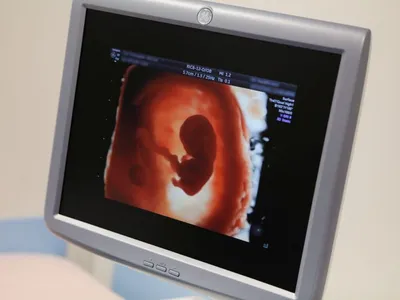

Maternitatea Bucur, din Capitală, centru pentru gravidele infectate cu coronavirus

Ministerul Sănătății și Comisiei de Obstetrică- Ginecologie a MS au decis ca Maternitatea Bucur din cadrul Spitalului Clinic de Urgență Sf. Ioan să preia eventualele cazuri ale femeilor gravide infectate cu noul coronavirus COVID 19.